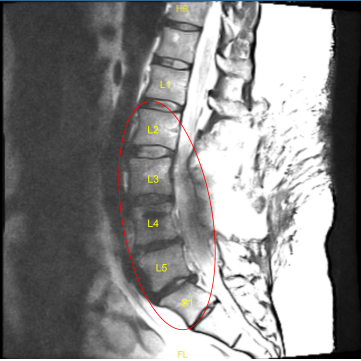

The patient was complaining of pain in both lower extremities. They had a history of L3 to S1 fusion done by another physician. Imaging studies showed good fusion mass from L3 to S1 but compression over L2-L3 segment with bilateral neural foraminal compression of L3 along with bony island formation over L3-L4 region with foraminal compression.

Status post posterior decompression the spinal canal from L2 through S1